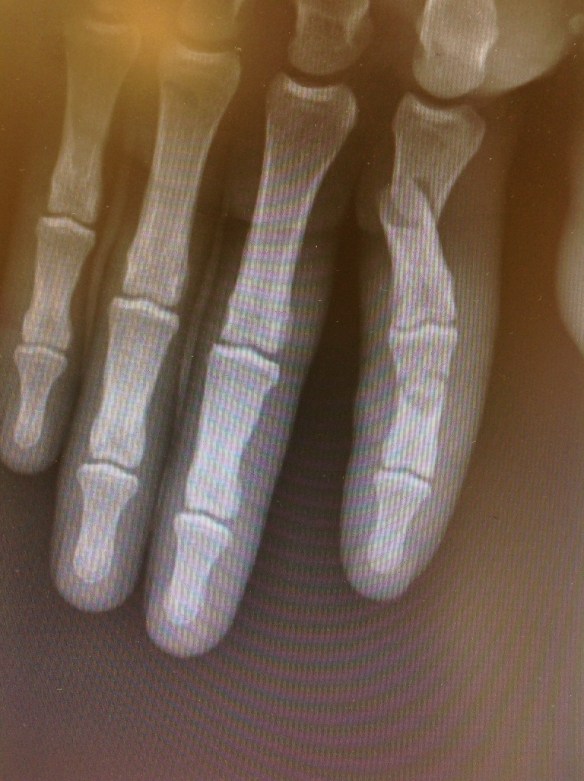

Paciente d 19 años que ingresó en nuestro centro afecto de Fractura de F2 del pulgar, fractura transversa de la F1 del índice, fractura conminuta de la F2 del índice con afectación del aparato extensor al mismo nivel.

Se procedió a síntesis anterógrada de la F1 con 2 agujas de Kirshner introducidas con la articulación metacarpofalángica en flexión máxima para no limitar la rehabilitación precoz.no coloqué placa de síntesis pues tengo comprobado que en la F1 las placas dan lugar a gran número de rigideces que obligan a su retarda y a tenolisis. En la F2 conminuta procedí a colocar placa con injerto de radio, en lidera rotación radial para facilitar la pinza término-terminal de un índice que por la lesión del aparato extensor asociada ya se preveía que tendría poca mobilidad de IFD. Se inició kinesiterapia activa autoasistida a los 3días postop.